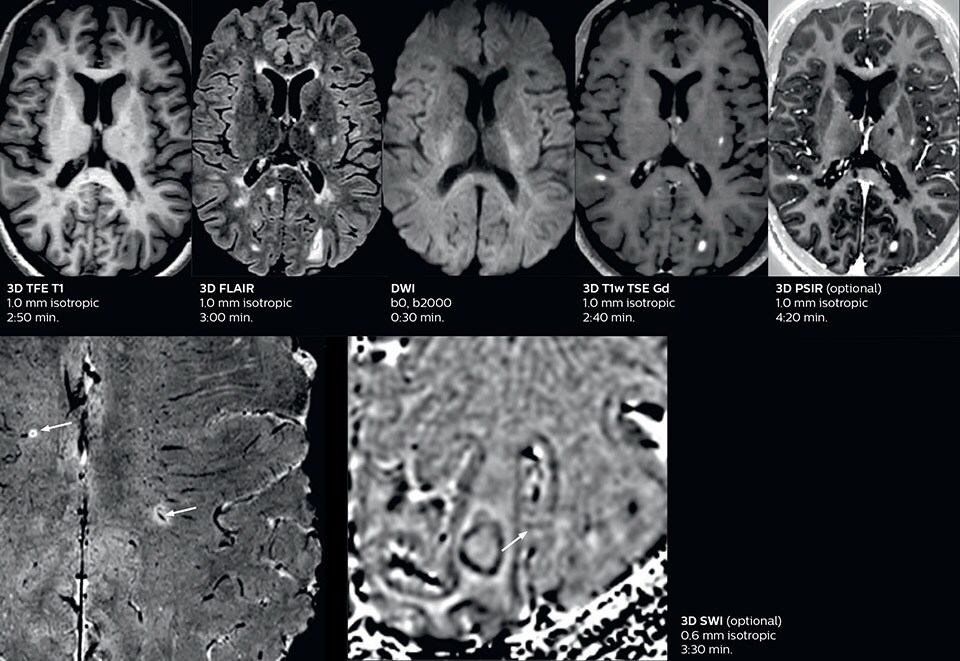

Ultimate precision at maximum speed with Dual AI

Take the leap forward with SmartSpeed Precise, the next generation acceleration technique that expands the proven Compressed SENSE and SmartSpeed technologies with a unique integrated Dual AI innovation, providing ultimate precision at maxiumum speed.

Read more

SmartSpeed Precise